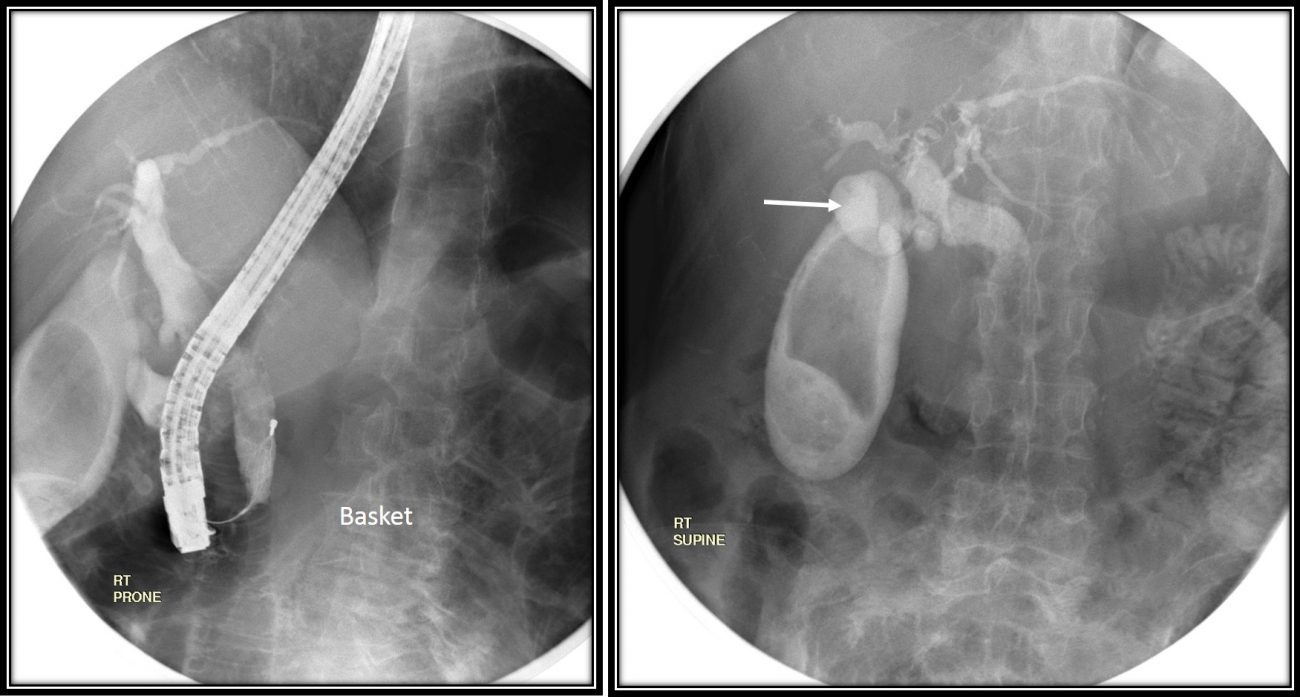

From radiologycases.my

Endoscopic removal of choledocholithiasis Radiology Cases Ercp For Gallbladder  Endoscopic retrograde cholangiopancreatography, or ercp, is a procedure to. Gallstones are hard pieces of material that can form in your gallbladder. These tests carry less risk than ercp. Endoscopy is the examination of an internal body part with an instrument called an endoscope. Learn about causes and treatment for this sometimes. This procedure involves placement of long plastic stents from. Ercp For Gallbladder.

Endoscopic removal of choledocholithiasis Radiology Cases Ercp For Gallbladder  Endoscopic retrograde cholangiopancreatography, or ercp, is a procedure to. Endoscopic retrograde cholangiopancreatography (ercp) is an invasive procedure used for the diagnosis and treatment of obstruction in the biliary. Endoscopic retrograde cholangiopancreatography (ercp) is an advanced endoscopic procedure in which a. Endoscopy is the examination of an internal body part with an instrument called an endoscope. Noninvasive tests include magnetic resonance. Ercp For Gallbladder.